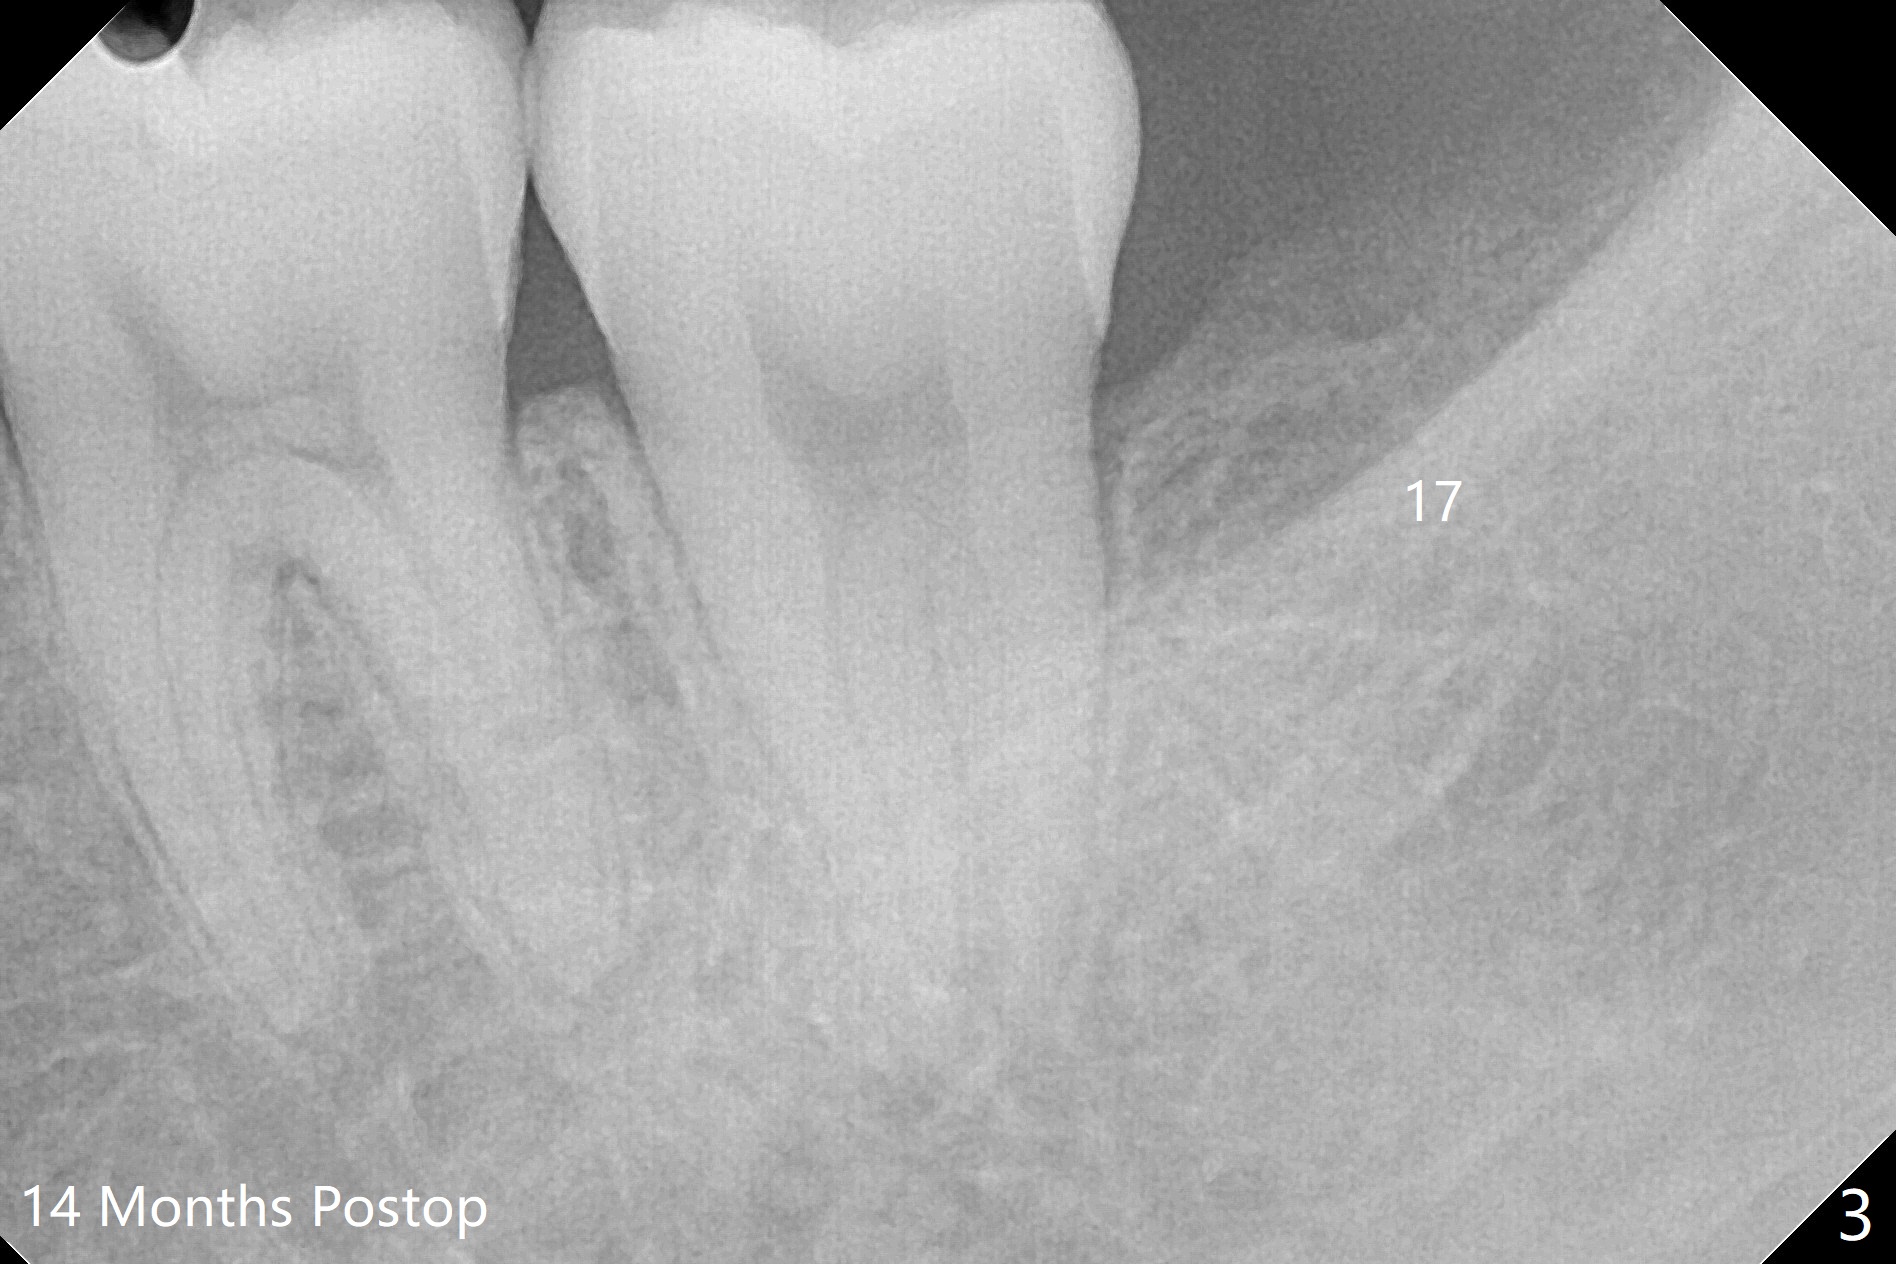

A 18-year-old woman has four of the 3rd molars extracted with placement of Osteogen Plug at #17 and 32 (Fig.1). Sockets seem to have healed 14 months postop (Fig.2,3).